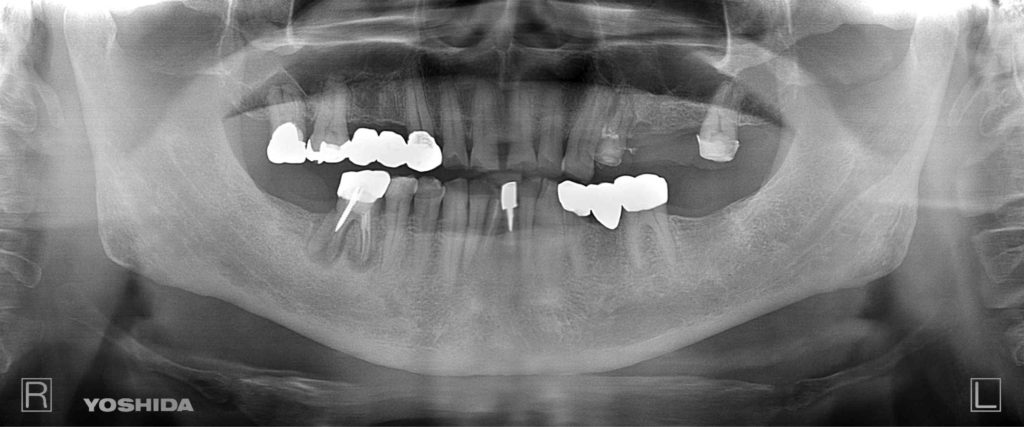

下記の症例は術前に綿密な治療計画を立案し、約10ヶ月ほどで咬合再構成を達成しました。

咬合再構成治療にかかる費用  約700万円(税抜)